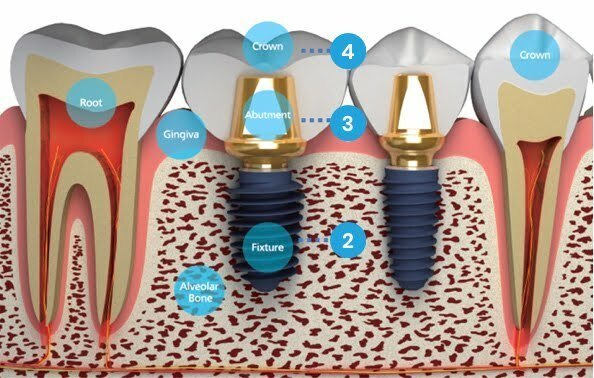

Dantų implantas – mažas titaninis varžtelis, kuris atstoja tikrą, nuosavą dantį. Po implanto įsriegimo, vyksta oseointegracija – implanto prigijimas. Oseointegracijos metu, implantas tvirtai sukimba su nuosavu kaulu ir tampa mūsų organizmo dalimi. Kuo implanto sukibimas su kaulu yra geresnis, tuo ilgiau implantas tarnauja kramtymo funkcijos metu.

Implanto sriegimas

Oseointegracijos arba implanto prigijimo laikas, vyksta nuo dviejų savaičių iki trijų mėnesių, priklausomai nuo esamos situacijos ir intervencijos dydžio. Kuo intervencija yra didesnė, tuo gijimas yra ilgesnis, todėl geriausia viską išspręsti saugiai, per vieną kartą.

Trečias žingsnis —

Implanto atrama

Implanto atrama – jungiamoji dalis tarp implanto ir danties vainikėlio.

Ketvirtas žingsnis —

Galutinis protezavimas

Dantų technikų laboratorijoje, jūsų individualių dantų atspaudų pagalba yra modeliuojamos būsimų dantų karūnėlės, siekiant jūsų naująją šypseną paversti kuo natūralesne.